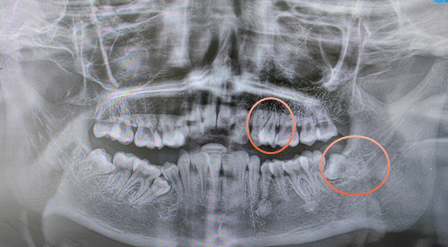

赵强了解后得知,小患者14岁,有一颗下颌埋伏阻生智齿和一颗上颌双尖牙需要拔除。但小患者因早产致发育迟缓及相应的并发症,从小到大数百次的求医治病,对口腔治疗充满了极大的恐惧,且小患者同时伴咽反射敏感,已经于多家医疗机构就诊,均未能完成治疗。这也给复杂牙齿拔除的操作带来了极大难度。

患儿术前X线片(标注处为本次治疗拔除的牙齿)